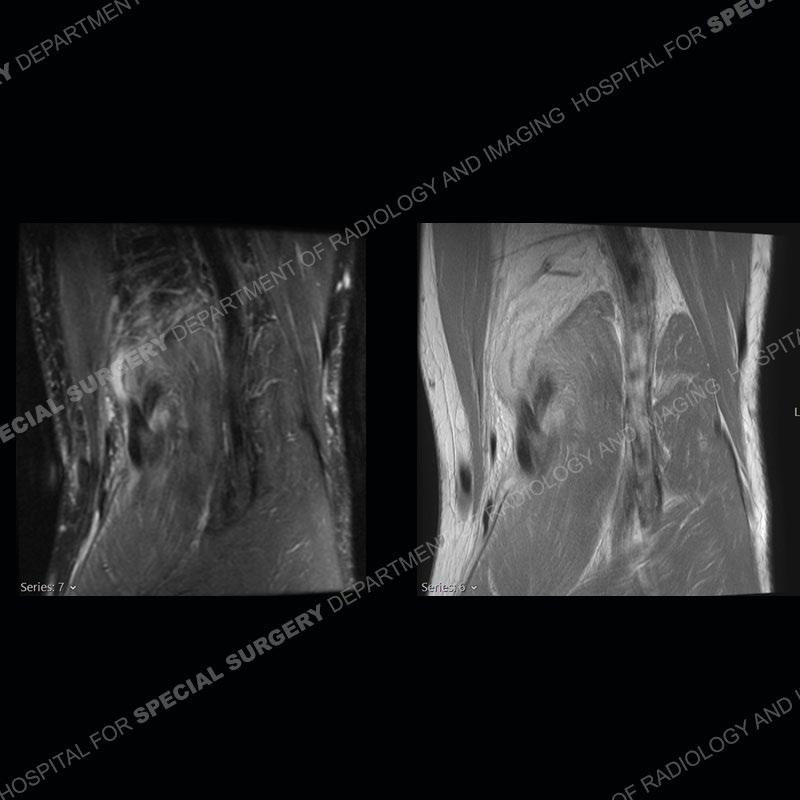

The radiographs show degenerative change of the medial compartment and a varus knee, but they are not germane to this case. No acute bony injury is present. The MRI shows edema of the posterior medial knee/soft tissue and a focal area of a partially disrupted low signal structure. The details are kept at a minimum in the findings of this case on purpose.

Fourth, use all imaging planes and different pulse sequences to make your diagnosis. The edema highlighted in this case can be seen as the obscuration of fat on the PD images but is much easier to perceive as the high signal on the IR pulse sequences. The actual disruption of the MHG myotendinous junction is only able to be seen on the axial images. On the sagittal and coronal images, we get a sense something is wrong but hard to be exact. Lastly, when you look at a study and something just seems off (as I would say the sagittal and coronal images do with that dark band of tissue posteriorly), listen to yourself and go through the study slowly and meticulously. Most of the time you will find you were right, and something indeed is present.